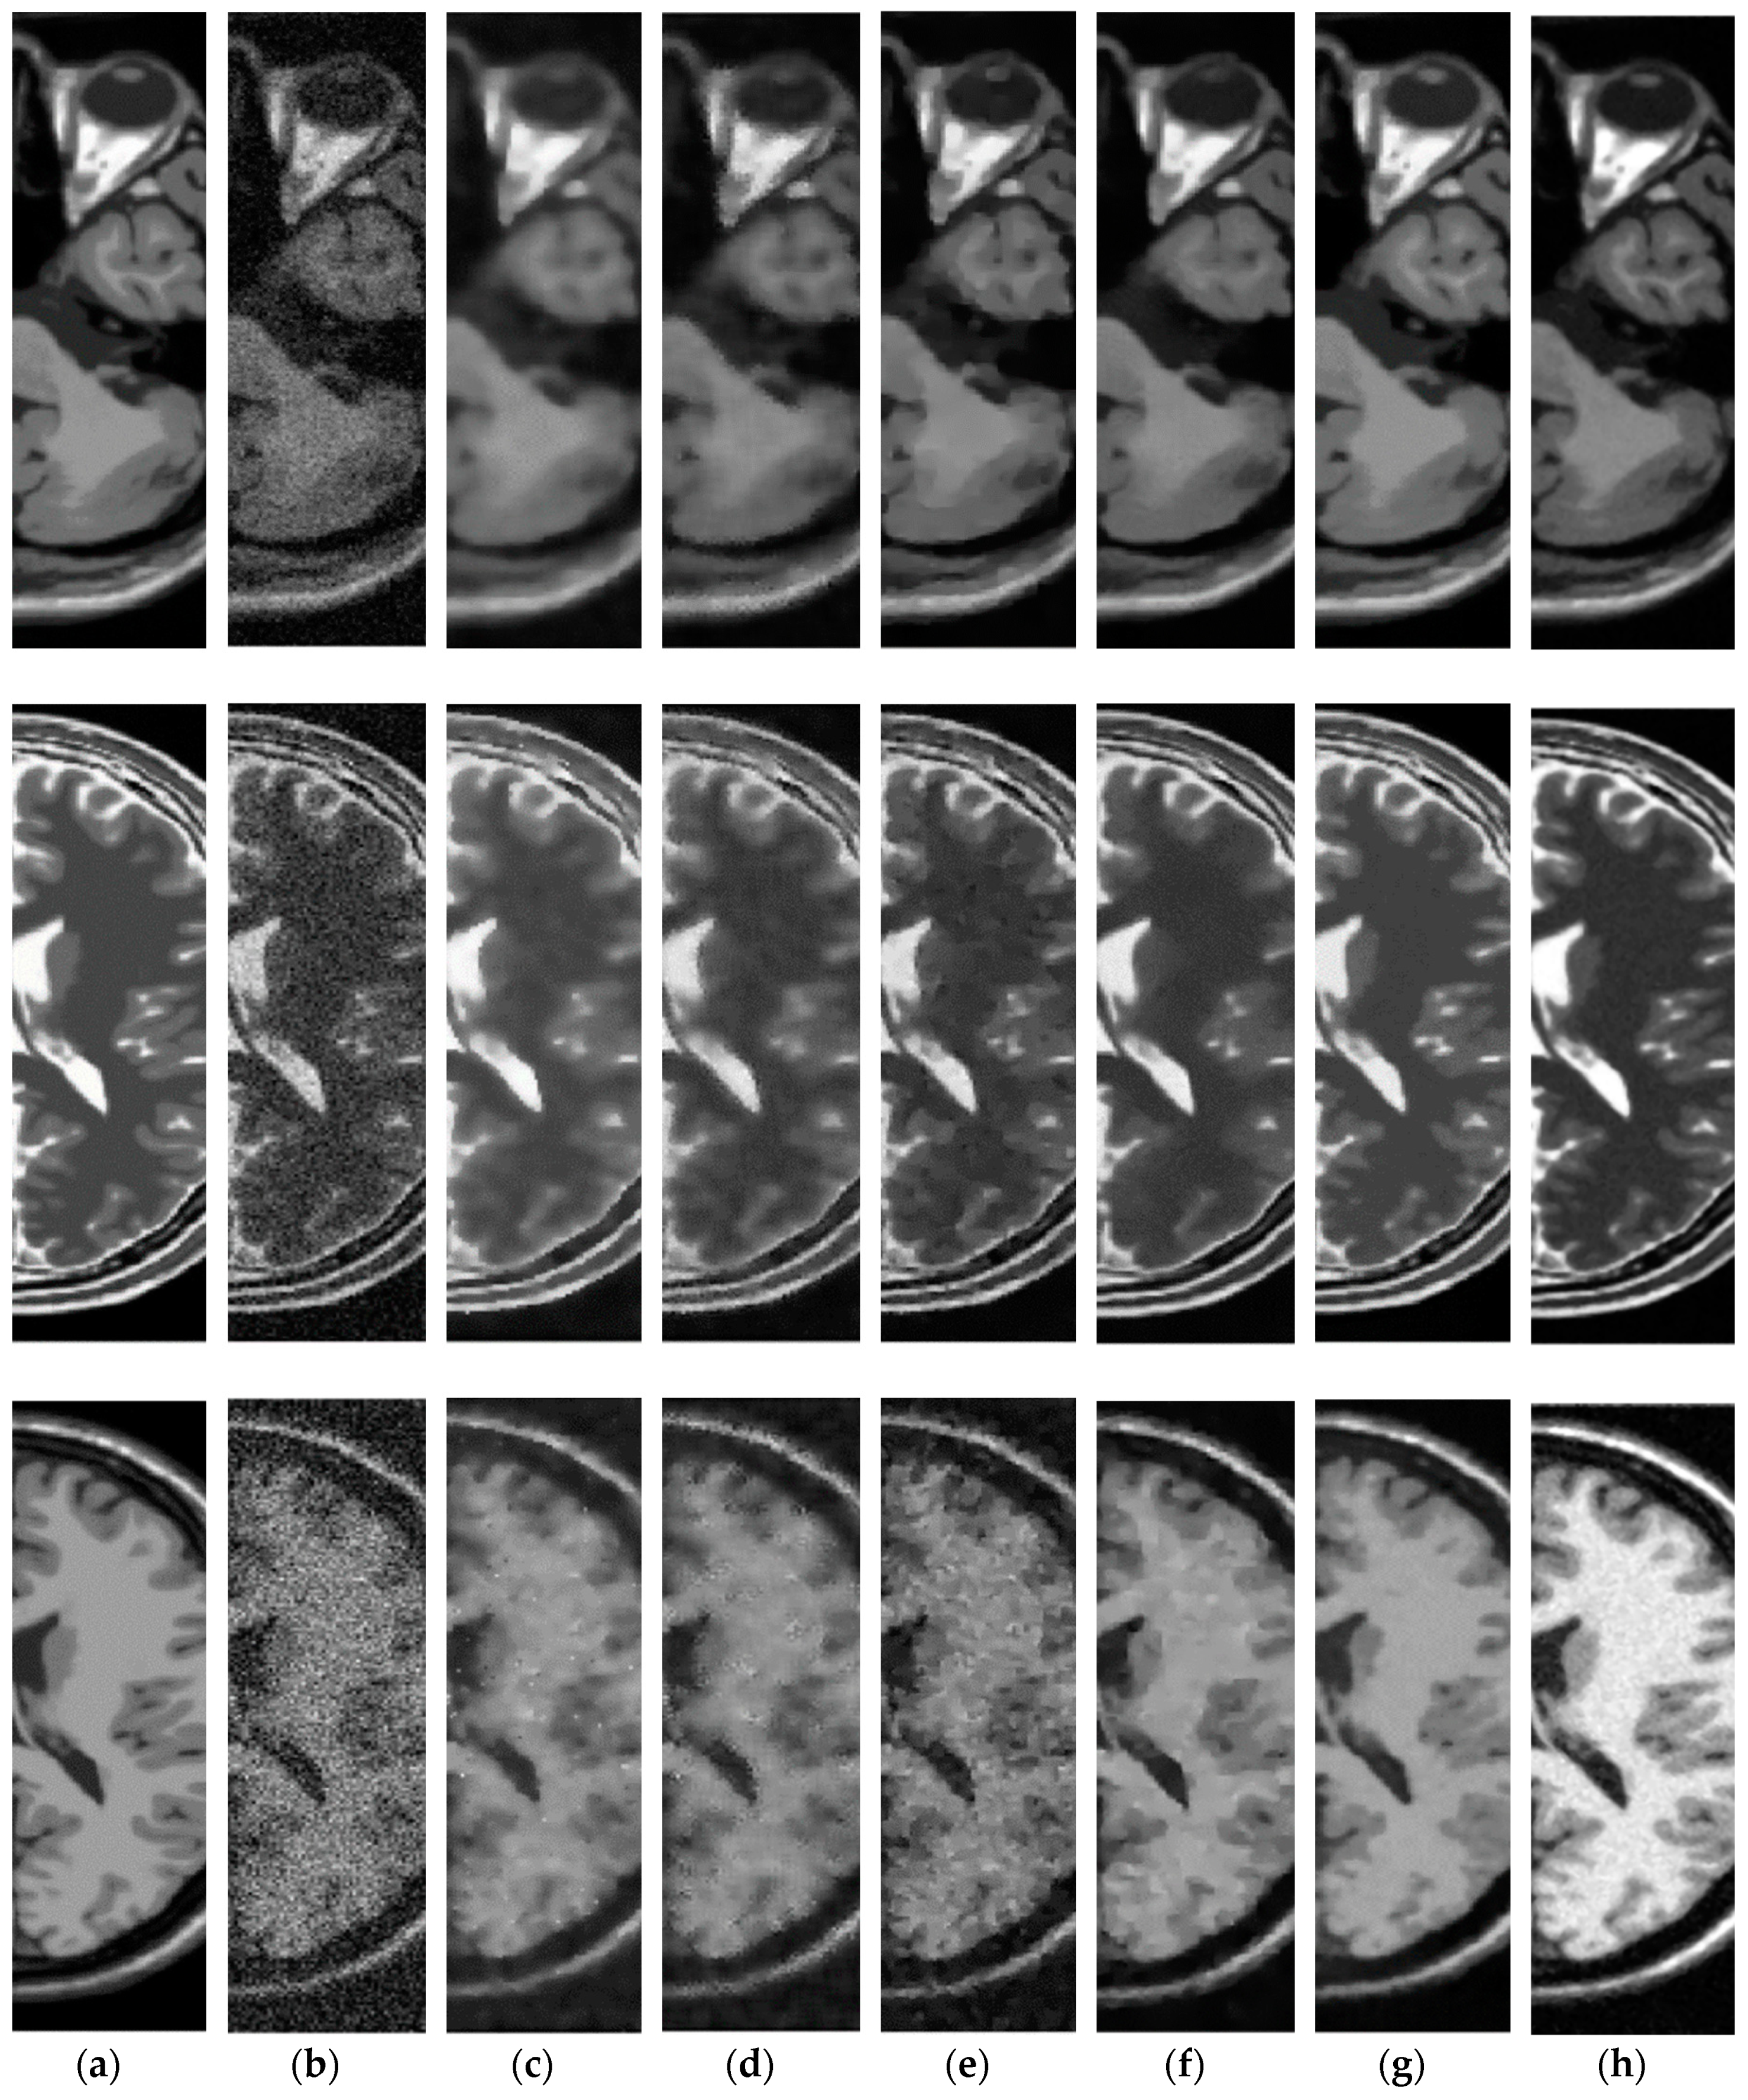

3.3. Comparative Performance in Simulated MRI